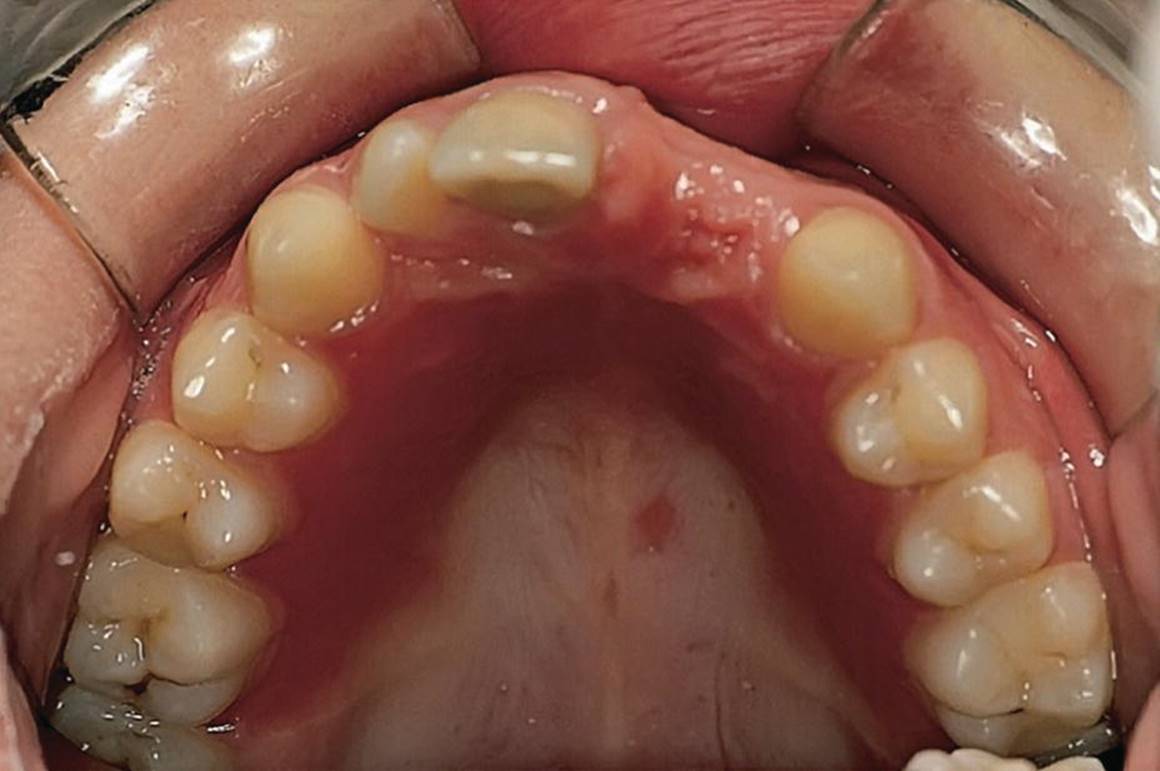

Epulides are by definition tumor‐like hypertrophic tissue formations located on the gingival mucosa. The etiology is often trauma or irritation in connection with tooth eruption or exfoliation. The size may vary from some millimeters up to several centimeters in diameter. They differ in surface texture, consistence and color, depending on the tissue composition. Pyogenic granuloma, peripheral calcifying granuloma, and peripheral giant cell granuloma (Figures 15.19, 15.20 and 15.21) are all examples of epulides. The treatment is excision, and the final diagnosis is confirmed by histopathologic analysis.

Figure 15.20 Peripheral calcifying granuloma.